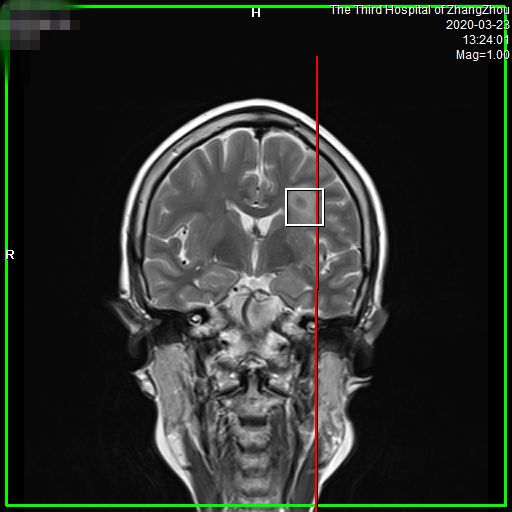

图像更清晰、诊断更精准

• 图像更清晰,病变细节显而易见。对中枢神经系统如头、颈部疾病,以及腹盆部、骨肌系统、乳腺等区域病变检出更敏感,可早发现、早诊断和早治疗。

波普分析(MRS)

• 信噪比高,能更早发现小病灶。有关数据显示,对于各类疾病,特别是神经系统和体部系统疾病,可以提前发现病灶,给患者治疗带来了充分的时间,大大提高了病变的诊断水平,让疾病无处可逃,为广大患者带来福音。